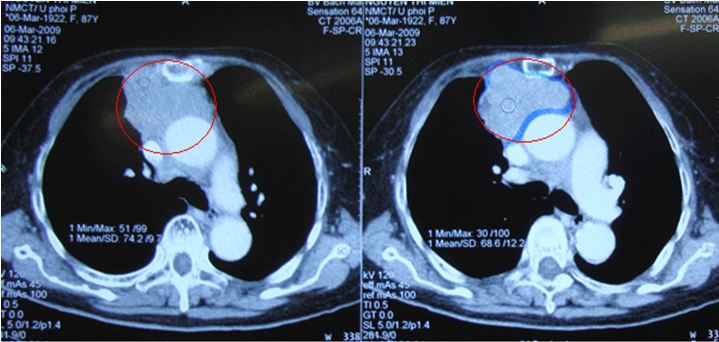

Kết quả chụp CT scanner lồng ngực:

Ngày 06/03/2009Ngày 14/04/2009Ngày 27/04/2009

Khối u tuyến ức

Khối u kích thước 63x48 mm ở trung thất trước trên, lệch sang phải, ngấm thuốc mạnh đồng nhất sau tiêm, không thấy vôi hóa hay thành phần mỡ trong khối

Khối vị trí tuyến ức ngấm thuốc cản quang sau tiêm, kích thước 50x30mm

Hình ảnh trước điều trị